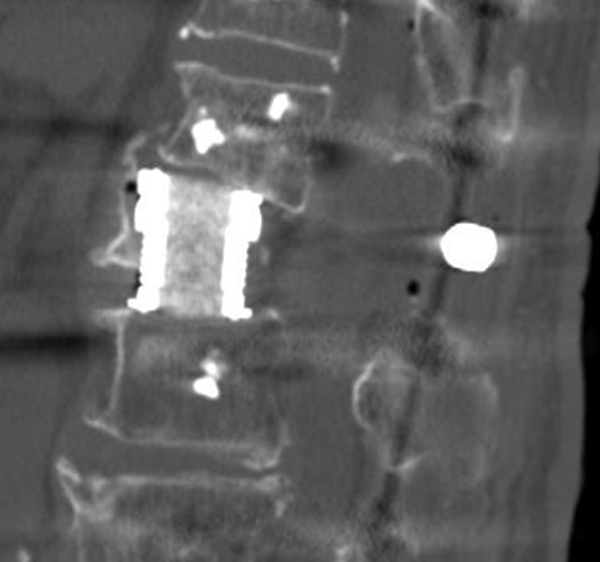

척추통증의 또 다른 흔한 원인으로 골다공증성 골절을 생각할 수 있다. 골다공증은 폐경기 이후의 여성과 고령의 환자에서 모두 관찰할 수 있는데 특히 여성의 경우 폐경 이후 급속한 골소실이 발생해 골다공증으로 이행되는 경우가 많다.

골다공증성 골절은 척추의 추체에서 발생하게 되는데 추체는 사람의 직립을 할 수 있게 하는 핵심 구조로 전체적인 체중을 지탱하는 역할을 한다.

이러한 추체의 압박은 그 자체만으로 만성통증으로 지속되는 효과뿐 아니라 간혹 골절편의 후방전위로 인한 신경압박으로 하지 마비를 유발하는 경우가 있으며, 또 다른 경우 신경병증을 유발하게 되고 심해지면 보행이 불가능해 질 수도 있다.

문제는 이러한 골다공증성 골절이 노년기에 발생하기 때문에 수술 선택의 폭이 넓지 않다는 데 있다.

따라서 골다공증이 의심되면 반드시 골절이 발생하기 전에 조기에 골다공증 치료를 받는 것이 중요하다.